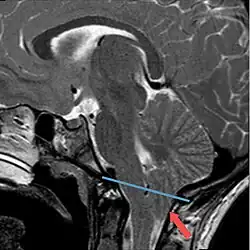

Als Chiari-Malformation wird eine Gruppe von Entwicklungsstörungen mit Verschiebung von Kleinhirnanteilen durch das Hinterhauptloch (Foramen magnum) in den Spinalkanal bei gleichzeitig bestehender verkleinerter hinterer Schädelgrube bezeichnet. Namensgeber ist der Pathologe Hans Chiari (1851–1916), der diese Störung erstmals beschrieb.[1] Die Bezeichnungen Arnold-Chiari-Malformation und Arnold-Chiari-Syndrom wurden von den Schülern des Pathologen Julius Arnold (1835–1915) propagiert, scheinen aber nicht gerechtfertigt, weil diese Gruppe der Entwicklungsstörungen von Arnold nur oberflächlich beschrieben wurde.[2]

- Typ I: Hier liegt eine Verlagerung der Kleinhirntonsillen vor. Als Komplikation kann es zu einer Syringomyelie kommen. Seltener werden knöcherne Fehlbildungen des Schädelbodens und der Wirbelkörper beobachtet. Patienten können durchaus beschwerdefrei sein.[3] Beschwerden treten nicht selten erst im jungen Erwachsenenalter auf. Neben Kopf- und Nackenschmerzen können dies z. B. Zeichen einer Schädigung des Kleinhirns, (z. B. eine als Ataxie bezeichnete Gangunsicherheit) oder des Hirnstamms (z. B. Schluckstörungen) sein. Chiari Typ I Malformationen können bei Patienten mit Ehlers-Danlos Syndrom vorkommen.[4]

Die Diagnosestellung erfolgt kernspintomographisch. Bei Feten können das so genannte Lemon sign oder Banana sign als sonografische Softmarker in der pränataldiagnostischen Sonografie ein möglicher Hinweis auf eine Chiari-Malformation sein.

Im Falle eines hydrozephalen Aufstaus bei herniierter Kleinhirntonsille wird eine Dekompression über einen subokzipitalen Zugang vorgenommen.